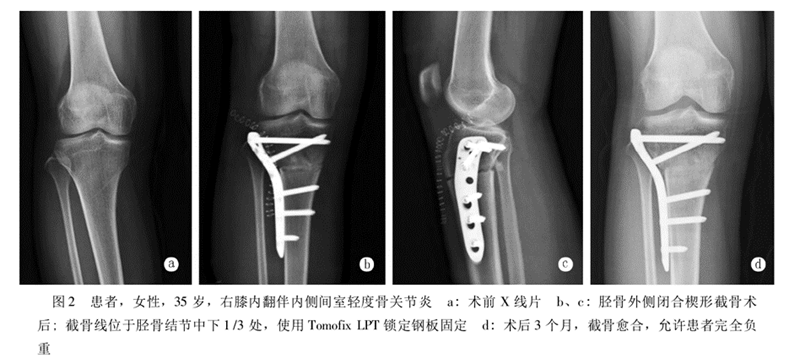

北京积水潭医院黄野教授等采用改良外侧闭合楔形胫骨高位截骨术治疗24例共35膝年龄均在45岁以下的膝内翻伴膝关节内侧间室轻度骨关节炎患者,术后平均胫股角(FTA)173.6°±2.4°,平均矫正11.0°±4.3°,截骨端均愈合,有1例延迟愈合。术后半年完全负重,无一例发生感染。2例出现腓总神经并发症(5.7%)。

采用改良外侧闭合楔形截骨,可以安全有效纠正内翻畸形,缓解骨关节炎疼痛,适用于年轻活跃的单侧或双侧膝内翻患者。但腓骨截骨的并发症仍然是需要考虑的因素之一。

选择不同的内固定,临床结果不尽相同。一组使用门型钉作为内固定的HTO病例,7.5年随访的满意度仅有60%;使用角钢版作为内固定的HTO病例,8.4年的随访满意度为61.1%;使用非锁定型Puddu钢板作为内固定的HTO病例,其并发症发生率高达43%;使用Tomofix锁定钢板作为内固定的病例,6.5年满意度高达98.5%。

Tomofix加压锁定钢板可以为截骨端提供牢固的内固定,稳定性好,可促进截骨端早期愈合,Tomofix的应用使HTO治疗内侧间室膝关节骨关节炎可获得良好的临床疗效。